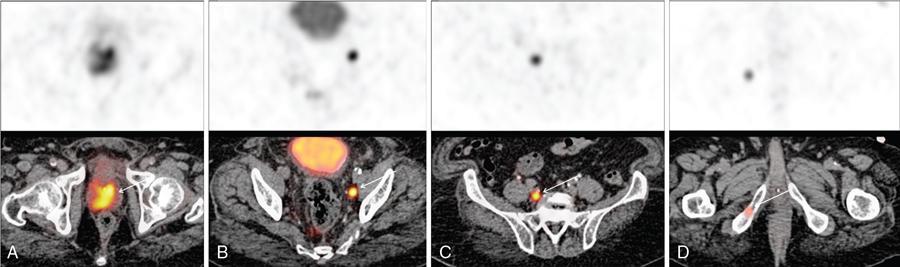

Karthik Ganesan, Disha Lokhandwala, Ujjwal Bhure, Jay Mehta Morphogenesis of the male genitourinary system is governed by the coherent interaction of three units, namely the Wolffian duct, urogenital sinus and foetal gonads. The Wolffian ducts are the embryonic precursors of the male internal genitalia, arising in the anterior intermediate mesoderm at 4 weeks of gestation. They elongate as a cord of cells that caudally extend to the urogenital sinus. Between 5 and 8 weeks of gestation, the urorectal septum divides the cloaca into a ventral compartment, which forms the urogenital sinus, and a dorsal compartment, which forms the rectum. The gonads form as epithelial thickenings on the ventromedial surface of the mesonephros and produce testosterone at 8 weeks of gestation, reaching a peak at 10–15 weeks. Under the effect of testosterone produced by the foetal testis, the prostate anlage forms at the tenth week of gestation. Precursor of the anlage begins with proliferation of solid epithelial buds from the epithelium of the urogenital septum into the adjoining mesenchyme in response to interaction of 5α-dihydrotestosterone with mesenchymal androgen receptors. As growth progresses, solid cords of epithelial cells are formed, growing into the mesenchyme in a specific three-dimensional arrangement (establishes the lobar divisions of the prostate gland). These solid cords develop a central lumen at birth and are lined by a layer of flat basal epithelium and a luminal layer of tall columnar secretory epithelium. Mesenchymal component forms the stroma, which has a large proportion of smooth muscle. Postnatally, the epithelial cords continue to arborize till puberty without any change in volume or glandular architecture. Although the foetal prostate has been described to have a histologically distinct peripheral zone (PZ) as early as 12 weeks of gestation, the mature zonal anatomy develops in concordance with the androgen surge at puberty. The most commonly utilized ultrasonographic technique for the evaluation of the prostate is via a suprapubic approach. The abdominal transducers used in this approach are relatively low frequency and while it offers the advantage of greater depth of penetration without intracavitary probe insertion; however, it does not depict the zonal anatomy and its chief application lies in volume estimation. Hence, transrectal ultrasonography (TRUS) completely outweighs the transabdominal approach in terms of depicting zonal anatomy, visualizing and localizing small lesions, demonstrating vascularity and performing biopsies. TRUS is performed using high frequency transducers (5–7.5 MHz) to optimize soft tissue resolution. An enema is administered 1 h prior to the examination to clear the field of insonation. Patient is positioned in left lateral decubitus, with knees bent toward the chest and ideally a digital rectal examination (DRE) is conducted prior to probe insertion. The transducer is first draped with a sterile barrier and lubricated, After insertion, the barrier is filled with 40–50 cc of water, making sure that no air enters. On completion, water is aspirated and the probe is withdrawn. The gland is initially scanned in the axial plane from the base to the apex, beginning at the level of the seminal vesicles, and the probe is gradually withdrawn to view the entire glandular parenchyma in axial sections up to its caudal aspect. This approach allows a cursory evaluation of glandular symmetry as both halves of the prostate can be evaluated simultaneously. Subsequently, sagittal views are acquired by rotating the probe across the transverse span of the gland, demonstrating the seminal vesicles, midline gland (visualizing both the apex and the base), with sequential scanning up to the contralateral margin of the gland. Sonographically, the prostatic capsule is seen as a smooth well-delineated, hyperechoic structure. With the newer ultrasound systems, the zonal anatomy can be delineated by TRUS; PZ appears echogenic relative to the central zone (CZ) and the transition zone (TZ), which are hypoechoic in juxtaposition (Fig. 11.12.1). Anterolaterally, the preprostatic venous plexuses are seen as anechoic tubular structures with intervening echogenic preprostatic fatty tissue. Glandular volume is estimated using an ellipsoid formula by obtaining the maximum anteroposterior, superoinferior and transverse dimensions and multiplying their product by π/6. Colour Doppler imaging is utilized to illustrate vascularity, as majority of the normal prostatic tissue (excluding the neurovascular bundles [NVBs] and pericapsular and periurethral regions) has symmetrical but sparse flow and an increased microvessel density raises the suspicion of prostatic carcinoma. However, the appearances of prostatic carcinoma can be variable on colour Doppler imaging, ranging from focal increase in vascularity around a nodule to an asymmetric increase in size and number of vessels on the affected side and conventional Doppler has found to elevate specificity by about 5%–10%. Additionally, Doppler imaging has also demonstrated some utility in distinguishing fibrotic tissue from local recurrence. However, vessels supplying cancerous tissue are of the order of 10–50 μm, which is well below the 1-mm resolution limit of conventional Doppler techniques. Contrast-enhanced colour Doppler imaging overcomes this limitation and facilitates imaging of microvessels, using intravenously administered microbubbles (less than 10 μm diameter) of an inert gas (sulphur hexafluoride) with a lipid or galactose shell, allowing quantification of blood flow in the cancerous microvessels. Additionally, these microbubbles act as vascular tracers and by monitoring the passage of a bolus injection through the tissue of interest, time–intensity curves are created. This permits the formulation of functional indices, including bolus arrival time, time to peak intensity, area under the curve and wash-in/wash-out curves. These indices can further extrapolate functional images, on a pixel-by-pixel basis, overlaid on grey-scale images. Quantitative methods to demonstrate perfusion are based on the destruction of microbubbles by high-power ultrasound pulses, and then observing the rate of microbubble replenishment in the field of interest to calculate flow rate. Halpern et al. utilized contrast-enhanced ultrasound and intermittent harmonic imaging with power Doppler, and exhibited an increment in sensitivity from 38% to 65% with a specificity of 80% in prostate cancer detection. Cadence contrast pulse sequencing (CPS) is a low-power multipulse imaging technique utilizing pulses with variable amplitudes and phases followed by a summation of the resulting echoes, permitting tissue suppression, allowing detection of even a small amount of contrast agents retained in the tissues. Real time elastosonography evaluates and quantifies tissue stiffness (Young’s modulus) by measuring strain under an applied stress (transducer compression) and maps areas of variable stiffness in colour-coded and grey-scale images simultaneously and shows potential in improving prostatic carcinoma detection. In a study comparing elastography and T2-weighted (T2-w) endorectal magnetic resonance imaging (MRI), similar sensitivity rates and negative predictive values (NPVs) were attained in the detection of prostatic carcinoma. Prostate gland is an inverted cone-shaped subperitoneal retropubic gland, with its base located rostrally and apex located caudally. The base is attached to the bladder neck and the apex sits on the urogenital diaphragm and abuts the medial surface of the levator ani muscles, namely the pubourethralis portion, which is separated from the inferolateral surfaces of the gland on either side by the prostatic venous plexus. Normal prostate gland measures approximately 4 × 3 × 3 cm, 15–20 g in weight, with a median volume of 11.5 mL (range, 1.6–20.6) in patients between 21 and 25 years and a median volume of 39.6 mL (range, 13–169.8) in patients between 38 and 83 years. The first comprehensive publication describing the anatomical subdivision of the prostate gland was in 1912 by Lowsley, based entirely on the embryonic glandular morphology at a series of gestational age groups. The budding prostatic ducts were seen to proliferate in five distinct clusters from the primitive urogenital sinus, which formed the basis of its lobar subdivision. It was divided into a ventral lobe (anterior to the urethra), two lateral lobes (lateral to the ejaculatory ducts), a posterior lobe (between the ejaculatory ducts) and a middle lobe (above the ejaculatory ducts). This classification had several shortcomings, the foremost being inclusion of only the embryonic prostate during its conception. Frank highlighted these aspects in 1953 and stated that no definite lobar boundaries exist in the adult prostate and further criticized the exclusion of periurethral glands (inner gland), identifying them as the sole site of origin of benign prostatic hyperplasia (BPH). The chief drawback of all research prior to 1968 was the lack of a concrete histological basis to support the seemingly arbitrary subdivision. McNeal was the first to ascertain histological heterogeneity within the glandular tissue and used it as the basis of his well-acclaimed prostatic zonal classification. The zonal anatomy of the prostate gland conceived by McNeal divided the gland into four distinct zones, namely the TZ, PZ, anterior fibromuscular zone (AFMZ) and the CZ (Fig. 11.12.2). McNeal used the plane of the distal urethra to describe the zonal relationships and divide the gland broadly into three parts, namely the base, midgland and the apex (Fig. 11.12.3). The improved understanding of the prostate anatomy coincided with the development of MRI in the late 1980s, which could depict the zonal anatomy, unlike ultrasonography (USG) or computed tomography (CT). Patterns of ductal growth and radiation from the prostatic urethra form the basis of the zonal anatomy of the gland. Ducts arising from the proximal urethral segment grow towards the urinary bladder. Tiny ducts which are confined by the preprostatic sphincter form the small periurethral gland, whereas ducts which develop distal to the lower border of the preprostatic sphincter extend laterally and then anteromedially to form the TZ. Ducts arising from the verumontanum in the vicinity of the ejaculatory duct orifices and are directed towards the base along the course of the ejaculatory ducts form the CZ, whereas ducts which arise from the lateral recess of the posterior urethral wall of the verumontanum and distal urethra radiate laterally to form the PZ and rostrally posterior to the CZ at the base of the gland. PZ is the dominant glandular component of the prostate gland comprising approximately 70% of the glandular tissue. On T2-w images, the normal PZ has a high T2 signal intensity (SI), owing to the abundant ductal and acinar elements with sparsely interwoven smooth muscle, and can broadly divided into three sections as per the sector map in Prostate Imaging Reporting and Data System Version 2.1 (PI-RADS v2.1), namely posterior medial, posterior lateral and anterior sections (Fig. 11.12.4). At the apex, the anterior sections have a horn-like morphology, curving anteromedially, to nearly encircle the urethra and abut the AFMZ. At the midgland level, the PZ comprises the posterior, both lateral and the anterolateral parts of the gland. At the base, the PZ is located posterior and superior to the CZ and TZ. CZ is an ovoid-shaped structure at the base of the gland, comprising approximately 25% of the glandular tissue, with its apex located at the verumontanum, surrounding the ejaculatory ducts. Beyond age 35, volume of the CZ starts to gradually diminish, as well as the CZ is compressed by the enlarged TZ. In the initial MR studies of prostate, the CZ could not be easily delineated from the TZ. Vargas et al. demonstrated in a population with a mean age of 60 years undergoing MR for prostate cancer assessment, the CZ was visible in 81%–84% of patients. Hansford et al. identified the CZ in 92%–93% of patients on T2-w images and 78%–88% of patients on apparent diffusion coefficient (ADC) maps. Histologically, substantial differences exist between the CZ and PZ, which reflect in the differential appearance on T2-w imaging. These differences are probably attributable to the differential origin, as the CZ is derived from the Wolffian duct, and the PZ and TZ are derived from the urogenital sinus. In the CZ, the acini appear larger and more irregular, with numerous epithelial covered ridges or septa project from the walls of the acini into the lumen, forming a characteristic Roman bridge architecture and intraglandular lacuna, with a prominent basal layer, crowded epithelial cells with granular eosinophilic cytoplasm, decreased luminal fluid and compact stroma. PI-RADS v2 has discouraged the use of the term central gland, as it is not reflective of zonal anatomy or reported on pathologic specimens. CZ demonstrates homogeneously low signal on the T2-w images and ADC maps and can, therefore, mimic prostate cancers. CZ is best identified on the coronal plane T2-w images paralleling the plane of the distal urethra, and appears as a symmetric paramedic paired structures surrounding the ejaculatory ducts from the base of the gland to the verumontanum (Fig. 11.12.5). TZ comprises approximately 5% of the glandular tissue of the prostate. On T2-w images, the TZ normally appears as a homogeneously hypointense structure surrounding the proximal urethra at the base and the midgland level; however, it can also demonstrate inconsistent SI, depending on the relative proportion of glandular and stromal elements (Fig. 11.12.6). Glandular hyperplasia produces higher SI (dominance of acinar elements and secretions), while stromal hyperplasia exhibits lower SI (dominance of muscular and fibrous elements). The TZ is easily demarcated from the PZ by a thick homogeneously low T2 signal surgical capsule, which becomes pronounced in BPH. With increasing age, the TZ demonstrates variegated signal on the T2-w images and ADC maps, due to differential growth of the stromal and glandular elements. AFMZ is a nonglandular muscular tissue that drapes the anterior surface of the gland, superiorly blending into the smooth muscles of the bladder neck and inferiorly extending to the prostatic urethra at the glandular apex. AFMZ is comprised of smooth muscles, which blends with the smooth muscle fibres surrounding the urethra, and rostrally merges with the bladder neck and preprostatic sphincter. High smooth muscle content of the AFMZ is responsible for the MR signature, where in it appears markedly hypointense on the T2-w images and ADC maps, and hypoenhances on the multiphase contrast series (Fig. 11.12.7). With the advancing age, temporal reduction in the size of the AFMZ is noted due to the compressive effects of the BPH. Capsule surrounds the prostate gland, anteriorly merging with the AFMZ anteriorly. Two discrete defects are identified in the prostate capsule, at the base of gland where the ejaculatory ducts enter the prostate and at the apex where in the stroma blends with the sphincter. The capsule is perforated along the anterolateral aspect by multiple vessels and nerves. The capsule appears as a thin dark rim surrounding the gland on the T2-w images and may reveal delayed enhancement on the postcontrast images (Fig. 11.12.8). Primary goal of radical prostatectomy (RP) is to achieve oncologic efficacy, both in terms of short-term and long-term clinical outcomes. However, as the majority of prostate cancers have an indolent clinical course, preservation of function in terms of continence and potency is equally important, and the key to this is a keen understanding of the fascial anatomy and neuroanatomy of the prostate gland. Fascial anatomy of the prostate gland is anatomically complex and poorly understood, and a thorough understanding of the interfacial planes is crucial to avoid mechanical or thermal injury to the NVBs. Periprostatic fascia comprises of a condensation of layers of connective tissue that encapsulate the gland and suspend it from anterior pelvic wall via puboprostatic ligaments. Laterally, the visceral and parietal endopelvic fascial layers fuse to form the fascial tendinous arch. Periprostatic fascia covers the prostate gland and capsule, comprises of two fascial layers, including an inner layer (prostatic fascia) and an outer layer (levator ani fascia), with thin interfascial planes separating these fascia from one another and the prostate capsule. Posteriorly, a continuous fascial layer known as Denonvilliers’ fascia covers the prostate and seminal vesicles. Distribution of periprostatic nerves is highly variable, with growing evidence of nerves both along the dorsolateral and ventrolateral surfaces of the prostate gland. Most of the periprostatic nerves are found posterolaterally; however, a significant portion of the nerves are located ventrally as seen by Eichelberg et al. (21.5%–28.5%) and Lee et al. (19.9%–22.8%). Although anatomic studies have confirmed the presence of ventrolateral periprostatic nerves, the exact clinical importance and functionality of these nerve fibres has not been proven. The cavernous nerves are situated posterolaterally and are the basis of nerve-sparing RP procedure proposed by Walsh and Donker. Unlike the initial theory of Walsh and Donker, few papers have proposed that the nerves are diffusely scattered along the surface of the gland in the form of a curtain or spray-like arrangement without clear bundle formation. Kourambas et al. assessed the precise relationship of the NVBs and cavernous nerves to Denonvilliers’ fascia and proposed that the nerves were not restricted posterolaterally, but were rather diffusely scattered within the fascia extending up to the midline (Lunacek et al., Takenaka et al.). On the basis of more diffuse arrangement of the periprostatic nerves, surgical techniques have been modified, resulting in a more anterior dissection called the ‘curtain dissection technique’ or alternatively a ‘superveil’ technique to preserve the NVBs within the lateral prostatic fascia. The NVB lies within areolar connective tissue surrounding the gland, which separates the capsule from the periprostatic fascia and provides a plane of dissection during nerve-sparing prostatectomy. Prostate gland is supplied and drained by periprostatic vessels, which also supply and drain the penis. Arterial supply of the gland is highly variable and is typically from branches of the internal pudendal artery, which course inferior to the gland prior to supplying the penile cavernosal tissue. Off late, these vessels have gained prominence in radiation-induced erectile dysfunction (ED) (potential vasculopathy), which have led to the development of newer vessel-sparing radiotherapy techniques. Further, with the advent of prostate arterial embolization in benign prostatic hypertrophy (BPH), the vascular supply of the gland is becoming increasingly vital to understand. Gland drains into the obturator, internal iliac, external iliac, common iliac and presacral lymph nodes. Dorsal venous complex is identified immediately ventral to the gland and also drains the penis. Periprostatic nodes are uncommon, are usually discovered near the base of the gland, and are only occasionally seen on MRI. Urethra is the principal anatomic reference point in the prostate gland. Urethra can be divided into a proximal segment and a distal segment, the point of differentiation being located at the verumontanum wherein the urethra makes an approximately 35-degree angulation. The angulation is highly variable and is further affected by the growth of the TZ. On MRI, the distal segment is more conspicuous vis-à-vis the proximal segment and appears a hyperintense core surrounded by a low signal rim on T2-w images. Preprostatic sphincter encases the proximal urethra from the base of the gland to the base of the verumontanum and merges with the AFMZ anteriorly. Verumontanum appears hyperintense on the T2-w images, lies within the distal urethral segment, beyond which the distal urethral segment is partially encircled by striated muscles which blend with the external sphincter beyond the apex of the gland. External sphincter is located distal to the apex is incomplete posteriorly and is anchored into the PZ and surrounds the membranous urethra. Damage to the external sphincter during RP or transurethral resection of the prostate (TURP) may lead to urinary incontinence. Seminal vesicles are paired structures identified posterosuperior to the base of the prostate gland, which appear as convoluted fluid-filled structures. Due to the high fluid content within the normal seminal vesicles, these structures appear as paired structures with intermediate signal walls surrounding a hyperintense core on T2-w images (Fig. 11.12.9). Vas deferens are paired structures located rostral to the base of the gland and anteromedial to the seminal vesicles and appear as cord-like structures with variable signal on the T2-w images. Duct of the seminal vesicle and vas deferens unite in the posterior aspect of the base of the gland to form the ejaculatory duct, which courses caudally to the verumontanum along the plane of the distal urethra, and drain into the orifices in the midconvexity of the verumontanum. Prostate-specific antigen (PSA) is a serine protease, secreted by epithelial cells of the prostate gland and has been found in normal, benign and malignant prostatic tissues. Traces of PSA have also been isolated from endometrial tissue, breast tissue, adrenal neoplasms and renal cell carcinomas; however, for all clinical purposes, PSA is considered as an organ-specific biomarker. Papsidero first demonstrated and quantified serum PSA, which steered the epoch of prostate cancer screening and early detection of prostatic carcinoma. Subsequent studies showed that PSA screening often led to overdiagnosis of low-grade prostate cancers, with no survival difference between the PSA screened and nonscreened groups. Additionally, PSA levels were found to be elevated in a spectrum of prostatic pathologies apart from carcinoma, including prostatitis and benign hyperplasia. The likelihood of overdiagnosis coupled with the lack of specificity set grounds for the longstanding PSA controversy. Did the benefits of screening outweigh the risks of overtreatment? To elevate the specificity of serum PSA testing, a plethora of indices were devised, including free PSA and total PSA, free-to-total PSA (f/t PSA) ratio, age-specific PSA, PSA velocity (PSA-V) and PSA density (PSAD). Serum PSA exists in three forms; the major form (approximately 75%) is bound to alpha-1-antichymotrypsin, followed by free PSA (constituting 5%–50% of serum PSA). The third form (PSA bound to alpha-2-macroglobulin) is not clinically relevant and cannot be detected by any commercial test. A study by Stenman et al. established that a higher proportion of bound PSA and hence a lower ratio of f/t PSA is associated with prostate cancer. Conversely, free PSA can be utilized during follow-up for men with an initial negative biopsy result, wherein declining free PSA with a persistently elevated total PSA would raise suspicion of a neoplastic aetiology. As per the ACS guidelines (Table 11.12.1) for early detection of prostate cancer, men with a 10-year life expectancy or higher should have the opportunity to make an informed (regarding benefits, risks and uncertainties associated with PSA screening) decision for serum PSA testing, with or without DRE. For those who choose to undergo PSA screening, subsequent screening interval is determined on the basis of baseline PSA value. For values below 2.5 ng/mL, screening interval can be extended to 2 years and for PSA between 2.5 ng/mL and 4 ng/mL, an individualized approach is adopted following risk assessment to recommend either further referral or screening on a yearly basis. A PSA level of 4 ng/mL or higher warrants referral for further evaluation or biopsy, for men at average risk for prostate cancer. Although age-specific PSA (Table 11.12.2) is not a component of the ACS guidelines, it is considered as a beneficial parameter in determining the need for biopsy. As there is an expected rise in PSA values with age, setting a lower cut-off value for younger men would increase the sensitivity of detecting organ confined cancers and a higher value in older men would increase specificity. aThere is no proven rationale for using a single PSA-V threshold value. PSA screening guidelines for treated localized prostate cancers are variable and the definition of biochemical (PSA) recurrence remains debatable. Due to this inconsistency, the Prostate Cancer Guidelines Update Panel recommended a standard definition for biochemical recurrence (BCR) after RP and set a cut-off serum PSA (acquired between 6 weeks and 3 months of surgery) of 0.2 ng/mL or greater, along with a second confirmatory PSA. While there is a significant fall in PSA values after RP and a single raised PSA is sufficient to raise suspicion of recurrence, postradiotherapy recurrence requires a rising trend rather than a single cut-off value. The ASTRO Consensus Panel defined postradiotherapy prostate cancer recurrence as three consecutive raises in PSA values after a baseline has been reached. A hiatus in this definition was that no specific time interval between consecutive increases in PSA was determined. In addition to its utility as a screening tool, PSA is also a good prognosticator when used in conjunction with biopsy Gleason score and clinical T-stage, and several pretreatment prostate cancer risk stratification systems are based on these indices. D’Amico et al. proposed a three-group risk stratification system in 1998, which categorized nonmetastatic (M0) carcinomas as low risk, intermediate risk and high risk. Low-risk prostate cancer was defined as 1992 AJCC T1/T2a, PSA ≤10 ng/mL and Gleason score ≤6. Intermediate-risk prostate cancer was defined as 1992 AJCC T2b, and/or PSA 10–20 ng/mL and/or Gleason 7 disease. High-risk disease included any one of the following: 1992 AJCC ≥T2c, PSA >20 ng/mL or Gleason 8–10 disease. In 2001, the GUROC published the results of a consensus meeting which categorized the groups as follows: low risk – 1997 AJCC T1–T2a, PSA ≤10 ng/mL and Gleason ≤6; intermediate risk – 1997 AJCC T1–T2, PSA ≤20 ng/mL and Gleason ≤7 not otherwise low risk and high risk – 1997 AJCC T3–T4 or PSA >20 ng/mL or Gleason 8–10. In due course, newer classification systems have been developed (Table 11.12.3), including the National Comprehensive Cancer Network (NCCN, USA), National Institute for Health and Clinical Excellence (NICE, UK), European Society of Medical Oncology (ESMO), American Urological Association (AUA) and the European Association of Urology (EAU). The NCCN guidelines also incorporate very low-risk (T1c, and Gleason score ≤6, PSA ≤10 ng/mL, <3 positive biopsy cores each ≤50% involved and PSAD of <0.15 ng/mL/g) and very high-risk (T3b–T4) categories. AUA, American Urological Association; EAU, European Association of Urology; GUROC, Genitourinary Radiation Oncologists of Canada; NICE, National Institute for Health and Clinical Excellence; CAPSURE, Cancer of the Prostate Strategic Urologic Research Endeavour; NCCN, National Comprehensive Cancer Network; ESMO, European Association of Urology; T, T-stage; GS, Gleason score; PSA, prostate-specific antigen. Note: Use of the 1997 TNM staging system (T2a one lobe involvement, T2b two lobes involvement, no T2c category). PSA, DRE and TRUS form the diagnostic triad for prostatic carcinoma. It has been well established that manipulations of the prostate gland, including prostatic massage, cystoscopy and perineal biopsy cause a potential increase in serum PSA levels. This raised the question of TRUS affecting PSA levels and it was found to cause a very small rise in PSA only in patients with prostatitis. The effect of DRE on serum PSA levels is also controversial, while some studies found a transient increase in PSA, others found no significant rise in PSA levels after DRE. Therefore, it is advisable to obtain blood samples for PSA testing either prior to DRE and TRUS or after at least 7 days. PSA-V refers to the change in PSA over time using serial measurements. Ideally, at least three consecutive measurements over at least 18–24 months should be used. Carter et al. first defined PSA-V and found that a value of 0.75 ng/mL per year or greater was indicative of carcinoma with a high sensitivity and specificity. Consequently, several studies disproved a definite relationship between PSA-V and prostate cancer, stating that there was no rationale behind a single threshold value for PSA-V. Further, it was found that calculating PSA-V was arduous and while elevated PSA values on serial examinations should raise alarm, there was no added benefit of formally calculating PSA-V. As per NCCN guidelines, the PSA-V cut-off should be based on the initial PSA value with a PSA-V of 0.35 ng/mL/y, when the PSA is ≤2.5 ng/mL and 0.75 ng/mL/y, when the PSA is 4–10 ng/mL PSAD was developed in order to correlate prostate volume and PSA values. The basis of PSAD was that cancer cells produce more PSA per unit volume than normal cells. It is calculated as PSA value divided by the prostate volume as determined by TRUS. This reliance on TRUS leads to interobserver variability and hence PSAD values would differ with the performing sonologist. The chief utility of PSAD is in the diagnostic grey zone of PSA values between 4 and 10 ng/mL and the most commonly used cut-off value is 0.15 ng/mL/cc. However, more recent studies have shown that a value of 0.08 ng/mL/cc has an NPV of 95% in predicting prostate cancer. Additionally, PSAD in conjunction with MRI (PI-RADS score) has proved to be a reliable prognosticator for Gleason score upgrading. The most significant application being avoiding unnecessary biopsies as PI-RADS scores of 1–3 along with PSAD values <0.15 ng/mL/cc showed no Gleason score upgrading on repeat biopsies. In summary, most guidelines recommend shared decision-making for screening of prostate cancer. Limited testing should be conducted in men with low PSA values and a lower life expectancy. The aim should be to overcome challenges posed by the inherent nonspecific nature of serum PSA and reduce superfluous testing, unwarranted biopsies and overdiagnosis. Reliance on parameters like PSA-V that do not have a proven scientific basis is avoidable. Whereas applications of PSA like PSAD along with MRI can greatly reduce patient burden by avoiding follow-up biopsies. Lastly, PSA has no role in assignment of a PI-RADS category, which is based on multiparametric MRI (mpMRI) findings alone. Several ‘novel biomarkers’ are now being developed which are more specific in detecting high-grade prostatic carcinomas. Other human kallikrein proteins have been identified, as prostate cancer biomarkers, of which, human kallikrein 2 (hK2) has shown a high specificity. While hK2 and PSA have an overlapping primary structure, malignant cells express hK2 to a higher degree than benign epithelial cells, particularly in aggressive cancers. Engrailed-2 (EN2) is an HOX gene family transcription factor seen exclusively in malignant prostate tissue, with a reported sensitivity and specificity of 66% and 88%, respectively. Annexin A3 is a calcium-binding protein measured in urine samples following prostatic massage, potentially reducing unnecessary biopsy in men with a PSA of 2–10 ng/mL. However, extensive prospective evaluation of these biomarkers is necessary to replace PSA testing in clinical practice. Positron emission tomography (PET)/CT has evolved over the last two decades to make a paradigm shift in the field of imaging, moving from morphological imaging to molecular level and completely changing the approach to how we view the disease. Though the main workhorse tracer in the field of PET/CT is 18-fluorine-fluorodeoxyglucose (18F-FDG), it has limitations with regard to prostate cancer, especially in indolent or well-differentiated ones. However, that void has been filled up by the new kid on the block and that is prostate-specific membrane antigen (PSMA)-based radiotracer. PSMA is a type II transmembrane protein with intracellular (19 amino acids), transmembrane (24 amino acids) and extracellular (707 amino acids) domains, which functions biochemically as a glutamate carboxypeptidase. After a ligand binds to PSMA, internalization occurs and it is either retained in lysosomal compartments or released into the cytoplasm. PSMA expression and localization in the normal human prostate is associated with cytoplasm and apical side of the epithelium surrounding prostatic ducts but not basal epithelium and neuroendocrine or stromal cells. Neoplastic transformation of prostate tissue results in the transfer of PSMA from the apical membrane to the luminal surface of the ducts. PSMA is an ideal target for molecular imaging of prostate cancer as its expression is significantly upregulated in prostatic carcinoma cells compared to benign prostatic tissue, in density (100 to 1000 times) as well as activity (8 to 10 times). PSMA expression increases with increase in Gleason score, stage and grade of tumour, with further increased expression with transition to androgen-independent/castration-resistant prostate cancer. PSMA-binding analogues, because of their high sensitivity and specificity, possess precise imaging characteristics required for critical decisions in the management of prostate cancer (PCa). The most commonly used PSMA radiotracer is 68Gallium-PSMA-11, followed by 18F-PSMA. The availability of 18F-labelled PSMA radiopharmaceutical has helped to advance the reach of PSMA PET imaging to wider locations owing to higher available amount of the radiotracer due to its production from a cyclotron, compared to 68Ga-PSMA which is eluted from individual in-house generator. Additional benefit is accrued with excellent image quality owing to optimized radiotracer doses, higher imaging statistics and favourable decay properties of 18F radioisotope. The normal physiological biodistribution of PSMA-based radiotracers is seen in lacrimal and salivary glands, liver, spleen, kidneys and intestine. Physiological activity is also seen in celiac and cervicothoracic ganglia. Unbound PSMA radiotracer is excreted by the kidneys into the urinary bladder. PSMA PET/CT has established roles of varying degrees in the imaging of different aspects of prostate cancer including primary diagnosis, staging, BCR after primary prostate cancer treatment (prostatectomy), identification and significance of oligometastasis, restaging and treatment response assessment and monitoring. PSMA PET/CT is useful at the stage of diagnosis in that subset of patients with tumour-negative biopsy samples, by contributing the useful molecular information to mpMRI, helping to precisely delineate suspicious lesions for targeted biopsies. In intermediate-risk to high-risk primary prostate cancer patients, PSMA-based imaging has shown improvement in detection of metastatic disease compared to the CT and mpMRI, which has led to reduced demand and dependence on additional cross-sectional imaging or bone scintigraphy. Furthermore, PSMA PET/CT has also established its clear advantage over conventional imaging in patients with biochemically recurrent prostate cancer with improved and increased detection of metastatic sites even at low serum PSA values. As it happens in cancer, biopsy is the standard of diagnosis and likewise in PCa, it is the multicore biopsy, which is the gold standard. However, because of its size, location, approach and sensitive and delicate nature, yield and accuracy can often be restricted, especially in inexperienced hands. The diagnostic yield of biopsy can go down as low as 40% and false negative (FN) rate can climb as high as 25%–30%. PSMA overexpression follows high-grade PCa cells and increases with Gleason score. In normal prostate tissue, PSMA to PSA ratio is about 1, which decreases in BPH, increases in primary PCa cells, further increases with intratumoural angiogenesis, higher in metastatic lesions than in primary PCa cells and further upregulated in castration-resistant situation. In a study by Litwin and Tan in 2017, the FN rate of multicore biopsy was around 21%–28% and about 15% of the cases were undergraded vis-à-vis final prostatectomy results. While the diagnostic accuracy of random multicore biopsy was around 76.3%, that of 68Ga-PSMA PET/CT was upward in the range of 85.5%. The role of PSMA PET/CT in the primary/initial diagnosis of prostate cancer is generally limited to clinically intermediate-risk to high-risk patients with negative biopsy or reluctance to biopsy or noncooperation or nonfeasibility and for confirmation and staging in clinically high-risk patients. In low-risk patients, metastatic spread is very unlikely and hence it is a relative indication at the time of initial diagnosis in low-risk patients. And, its role in screening is variable and debatable (Fig. 11.12.10). Staging is crucial as it has considerable influence on deciding further line of management and treatment choices, which includes RP, radiotherapy or palliative systemic treatment, deciding on the extent of the pelvic nodal dissection during surgery, planning the radiotherapy field and consideration of multimodal therapy. Accurate staging helps to make the most appropriate choice of treatment modality (Fig. 11.12.11). In a meta-analysis of five studies with histopathology as gold standard, which included 216 patients, the per-lesion sensitivity of 68Ga-PSMA PET/CT ranged from 33% to 92% (33% value being an outlier due to the retrospective analysis based only on the reports, in absence of the images) with higher specificity of 82%–100%. For T-staging, PSMA PET/CT showed a significantly higher tumour detection rate of 92% vis-à-vis 66% with MR alone. In regard with N-staging, the majority of metastatic nodes from prostate cancer are small subcentimetre-sized, less than 8 mm, which are overlooked, missed or inconclusive on morphological imaging (CT and MRI) (falling below size criteria for morphological imaging). Accurate N-staging is important because lymph node involvement is a critical prognostic factor in cancer management, and precise pelvic nodal clearance could be curative and could make a difference in treatment success and long-term outcome in prostate cancer (Fig. 11.12.12). Also, accurate prediction of pelvic nodal metastases may spare nodal dissection, shorten surgical time and in turn help to reduce undesirable complications. In one study from 2016 involving 130 patients with intermediate-risk to high-risk prostate cancer, the metastatic nodal detection rate by 68Ga-PSMA PET was around 66% compared to 44% with MRI. PSMA PET has shown superior predictive value for surgical response over Gleason score, pT stage and PSA (at the time of imaging). In a literature overview by Luiting et al. in 2019 involving 9 retrospective and 2 prospective studies, the specificity of PSMA PET/CT in detection of pelvic nodal metastases before initial treatment reached as high as 80%–100%. PSMA PET/CT increases the confidence level in the evaluation of nodal metastases and an NPV reaching up to 86%. With imaging becoming more precise and adding different modalities together, the question arises about the tiny nodes less than 5 mm size. In a study by van Leeuwen et al. in 2017, the mean size of missed lymph node metastases was 2.7 mm. In a recent study by Ferraro et al. in 2020, about the impact of PSMA PET staging on clinical decision-making in intermediate-risk to high-risk prostate cancer patients, PSMA PET provided new information in 36% of patients and this helped to change treatment decision in nearly 27% of patients, which means in every fourth patient they studied. PSMA PET in combination with CT or MRI can achieve complete and precise Tumor, Nodes and Metastases (TNM) staging including staging of local tumour, nodal assessment and bone and organ/visceral metastases, in one single imaging session, with improved accuracy and better outcome, and in turn leading to precise treatment planning, eventually superseding conventional imaging. Accurate localization of prostate cancer lesions in patients with BCR is a major challenge. Especially at low serum PSA values (as low as less than 0.5 ng/mL), the precise determination of localized disease and metastatic spread is of great importance for further disease management. Conventional imaging modalities including CT scan or bone scintigraphy have limited detection rate for metastatic disease at low serum PSA values in this setting of BCR. PSMA PET/CT imaging plays a very valuable role in the evaluation of BCR (Fig. 11.12.13), which is indeed very critical and important aspect in prostate cancer management. The international consensus on BCR includes PSA >0.2 ng/mL for two times after prostatectomy, or PSA nadir + 2 ng/mL after radiotherapy or brachytherapy. With the incorporation of PSMA PET/CT in the imaging armamentarium, the overall detection rate for local recurrence as well as metastases with BCR after prostatectomy reached up to 90%. The detection rate increases with rising PSA level, jumping over 90% with PSA level going above 1 ng/mL. In a homogeneous consecutive cohort of 248 patients with BCR after RP with mean serum PSA value of 1.99 ng/mL, studied by Eiber et al., 68Ga-PSMA PET/CT showed detection rates of 57.9%, 72.7%, 93.0% and 96.8% for patients with serum PSA values of 0.2–<0.5 ng/mL, 0.5–<1 ng/mL, 1–<2 ng/mL and ≥2 ng/mL, respectively. Tumour Gleason score or androgen deprivation therapy (ADT) did not significantly influence the detection rates (Fig. 11.12.14). These detection rates for 68Ga-PSMA PET are substantially higher than those reported for choline-based PET radiotracers, which fell between 19% and 36% at serum PSA levels of <1.5 ng/mL. The improved detection rates are due to the incremental value of molecular imaging as 68Ga-PSMA PET exclusively showed findings not evident on diagnostic CT in 32.7% of patients with information about additional involvement of different anatomical region in 24.6%. A high PSA-V and short PSA doubling time showed a tendency towards increased detection rates, though not statistically significant. As salvage radiotherapy is most effective at low serum PSA values, optimized radiotherapy planning with precise definition of target volume for concerned lesions for appropriate boost radiotherapy can be achieved with the help of PSMA PET/CT imaging. Lesion detection rate with PSMA PET/CT in the setting of BCR: PSMA PET/CT imaging helps to identify patients with oligometastatic disease who are suitable for salvage therapy with PSMA-radioguided surgery. PSMA radioligands, by the virtue of their high sensitivity and specificity, can be used for intraoperative tracking of even small metastatic prostate cancer lesions that can be well localized and subsequently removed using this radioguided surgery for salvage procedures. Identification and treatment of oligometastatic disease (3 to 5 positive sites) with targeted therapies such as surgery or radiotherapy may allow deferral of systemic therapies such as ADT, thereby delaying and reducing potential morbidity associated with systemic salvage therapy. The fusion of PSMA PET and MRI, instead of CT, may improve detection rates further in patients with very low serum PSA values (<0.5 ng/mL). The addition of mpMRI to PET can improve the diagnostic accuracy because of the higher soft tissue resolution and detection efficacy of mpMRI for local recurrence compared to CT. Advantages of PET/MRI include excellent anatomical and zonal resolution of the prostate gland with T2-w sequences, and additional useful information about suspicious lesions from functional MRI sequences like diffusion-weighted images (DWI) and dynamic contrast-enhanced (DCE) imaging. Early and accurate detection of tumour burden helps to plan further management strategy including salvage pelvic radiotherapy or salvage nodal dissection and eventually improve the prognosis. PSMA PET/CT also plays an important role in mapping the overall tumour burden, and separating oligometastatic disease from multiple metastases (Fig. 11.12.15). PSMA PET/CT also plays an important role in monitoring the treatment efficacy as well. 99mTc-methylene diphosphonate (99m Tc-MDP) (gamma camera-based radiotracer – single-photon emission computerized tomography (SPECT)/CT) or 18F-sodium fluoride (NaF) (PET/CT-based radiotracer) are bone-specific biomarker of osteoblastic activity. 18F-NaF has superior diagnostic performance compared to 99mTc-MDP (phosphonates) bone scintigraphy in detection of bone metastases, because of different radiotracer characteristics (different energy levels) and different scanners (PET/CT scanners vs conventional gamma scanner) leading to better resolution and clarity with 18F-NaF PET/CT scans. NCCN recommends bone scintigraphy in patients with PSA levels of more than 20 ng/mL or patients with T2 disease with PSA levels more than 10 ng/mL. However, their routine use in clinical practice is limited by relative lack of sensitivity and specificity vis-à-vis PSMA PET/CT and also not able to assess soft tissue lesions, which is possible with PSMA PET/CT (Fig. 11.12.16). Bone scans often fail to detect a lesion when PSA is less than 10 ng/mL in the setting of PSA recurrence post-RP, whereas PSMA PET/CT has been sensitive in the detection of lesions even at the PSA level of less than 0.5 ng/mL. Prostate cancer is a leading cause of cancer-related death in men; however, many patients with the prostate cancer do die of other causes. Hence, it is of paramount clinical importance to accurately risk stratify patients, to distinguish those with low risk to intermediate risk who could be managed conservatively or alternatively those with high risk for morbidity and mortality who would benefit from an aggressive line of therapy. Detection, risk stratification, staging, individual centred management, monitoring and surveillance of prostate cancer have undergone substantial evolution with time. MRI of the prostate gland was first described by Hricak et al. in 1983 and for long was used for staging patients with biopsy-proven prostate cancer and also occasionally served as a problem-solving tool. With recent advancements in MR technology, multiparametric imaging has become the cornerstone of the prostate cancer management, aiding in detection, characterization, risk stratification, biopsy guidance, surveillance and monitoring. This has been further enhanced and strengthened with the introduction of PI-RADS v2.0 in 2015 which helped standardize communication between the radiologists and urologists, and aided in the clinical decision-making process. As the role of MRI has expanded from detection to surveillance and monitoring, the entire clinical context needs to be available to the radiologist prior to performing an mpMR in order to optimize reporting. Both the imaging techniques and its interpretation may vary with the clinical context. In patients with no prior history of therapy, both T2-w images and DWI have a greater impact on reporting and interpretation, whereas in patients with prior therapy T1-w DCE imaging plays a more critical role in interpretation. In routine clinical practice, PI-RADS v2 recommends that PSA levels, detailed results of prior prostate biopsies and therapies be available to the radiologist at the time of performing and interpreting MR findings. Postbiopsy intraglandular haemorrhage occurs after image-guided prostate biopsies and is a confounder, which may obscure an underlying cancer. The greater extent of haemorrhage is attributable to the production of citrate within the prostate gland, which acts as an anticoagulant. The rate at which haemorrhage resolves is highly variable, often fully resolving in a shorter period in some patients and alternatively persisting for many months. Haemorrhage exclusion sign is a useful imaging finding, which may allow the radiologist to localize prostate cancer, as cancerous tissue has low levels of citrate and hence the propensity to haemorrhage in cancerous tissue is lower vis-à-vis benign glandular tissue. In addition, postbiopsy haemorrhage produces milder hypointensity on the T2-w and ADC maps vis-à-vis cancerous tissue. Ideally, a timeframe of 6–8 weeks has been suggested between the biopsy and the mpMRI. However, in routine clinical practice, the need to accommodate patients immediately postbiopsy or within a shorter time frame does exist, as the information provided by mpMR does overweigh the impact on haemorrhage on intraglandular tumour detection. Rectal over distension with faecal matter or gas impairs the quality of prostate mpMRI and especially seems to exacerbate artefacts on DWI. These issues seem to impact imaging with phased array coil rather than endorectal examinations. To avoid these artefacts, patients may be instructed to evacuate shortly before the examination, use a laxative or minimal enema prior to the procedure, have a preparatory enema or use antispasmodic agents to reduce potential artefacts from bowel peristalsis. Though various approaches do exist to adequately empty the rectum and minimize the artefacts, there is a lack of consensus on the optimum technique. mpMRI of the prostate gland can be performed on a 1.5 Tesla (1.5 T) or a 3 Tesla (3 T) scanner. Vastly improved signal-to-noise ratio (SNR) is the critical advantage of a 3 T scanner over a 1.5 T scanner, which in terms of prostate imaging translates into acquisition of high quality images with improved spatial and temporal resolutions, and also acquisition of higher quality functional sequences for quantitative imaging. Therefore, increasing field strength results in better detection and characterization of prostate cancer. On the contrary, higher field strength can amplify susceptibility artefacts arising from rectal air or metallic prosthesis. Other than field strength, many factors impact image quality and resolution including scanner model, gradient quality, slew rate, coil architecture and design and the sequence MR acquisition parameters. Prostate examinations are performed using a phased array coil placed over the pelvis. In certain institutions, an additional endorectal coil may also be used to achieve a higher SNR which improve the visualization of the prostate capsule and NVBs. Utilization of endorectal coils has certain drawbacks and results in patient discomfort, increased cost and scan duration and causes gland distortion. Endorectal coils improve imaging quality and local staging; however, with recent advances in coil technologies, phased array surface coils do provide similar high quality resolution images, which allows for accurate local staging. Currently, PI-RADS v2.0 does not insist on the use of endorectal coil and allows radiological practices to select hardware and optimize sequences that are most appropriate for the given clinical setting. mpMRI of the prostate gland is a combination of anatomical (morphological) and functional sequences. As per the PI-RADS v2 guidelines, the key sequences recommended include triplanar high-resolution axial T2-w images, high b-value axial DWI and ADC map and axial T1-weighted (T1-w) DCE images. High-resolution axial T2-w images and DWI are used to initially localize the ‘index lesion’ in the prostate gland. High-resolution sagittal and coronal T2-w images aid in colocalization of the ‘index lesion’ in terms of its spatial relationship with the gland. High-resolution T2-w images are the principal sequences of mpMR and are acquired with a small field-of-view (120–140 mm) in sagittal, oblique axial and oblique coronal planes. The high-resolution oblique axial and oblique coronal T2-w images are acquired orthogonal and parallel to the long axis of the prostatic urethra. These anatomical images provide exquisite demonstration of prostatic zonal anatomy, prostate capsule and periprostatic structures, which allows to accurately detect extraprostatic extension. An alternative to the acquisition of three separate T2-w sequences is the acquisition of a single volumetric 3-D T2-w imaging sequence with small near-isotropic voxels, which can then be retrospectively reconstructed in any plane. However, few concerns regarding the 3-D acquisition exist, including long acquisition time that may predispose to greater motion artefacts, reduced in-plane resolution and superimposed T2 and T1 contrast, which may diminish lesion conspicuity. PZ: Normal PZ has high SI on the T2-w images due to its high water content. Most prostate cancers exhibit low SI on T2-w images; however, mucinous adenocarcinomas may have a predominantly high SI. Low SI in the PZ may appear focal or diffuse and is not sine qua non for cancer, and may be seen in chronic prostatitis, glandular atrophy, postbiopsy haemorrhage or represent posttreatment sequelae. Rosenkrantz et al. demonstrated a diagnostic accuracy of 60% for T2-w imaging and showed that T2-w images is only moderately accurate for the detection of cancer and is not adequate for the diagnosis and localization of prostate cancer. T2-w images exquisitely demonstrate important morphological features of the lesion, which may aid in differentiation of cancerous tissue from its benign mimics, including size, shape and margin. Morphological features may overlap between benign lesions and low-risk to intermediate-risk cancers, but are very conspicuous in high-risk cancers. Benign lesions tend to appear linear-shaped or wedge-shaped and have indistinct margins, whereas prostate cancer appears as focal, crescentic or lentiform-shaped lesions. Lesion size is also a predictor for benign versus malignant, with larger lesions more likely to represent prostate cancer with a greater propensity to develop extracapsular extension. T2-w imaging is not the dominant sequence used to assess lesions in the PZ. T2-w PI-RADS v2 categories for PZ lesions are based on the SI, size, shape and margin of the lesion. PI-RADS category 1 is assigned to a homogeneously high SI normal PZ. PI-RADS category 2 lesions are linear-shaped or wedge-shaped, or present as areas of mildly low SI with indistinct borders. PI-RADS category 3 lesions have moderately low SI, but are heterogeneous or noncircumscribed are considered indeterminate. PI-RADS category 4 lesions have a high probability for clinically significant prostate cancer, are focal mass-like, circumscribed, exhibit homogeneously moderate to marked low SI and are less than 1.5 cm in size and do not exhibit extracapsular extension. PI-RADS category 5 lesions have a high probability for clinically significant prostate cancer, are focal mass-like, circumscribed, exhibit homogeneously moderate to marked low SI, are greater than or equal to 1.5 cm in size and/or exhibit extracapsular extension. Findings of extraprostatic extension (EPE) include focal capsular bulge with whiskering of the periprostatic fat, capsular irregularity, NVB asymmetry, obliteration of rectoprostatic angle and seminal vesicle invasion (SVI). TZ: Accurate detection and characterization of focal lesions in the TZ is the greatest challenge in the assessment of mpMRI. The challenge is most profound in middle age and elderly patients, the same population subset at risk for developing prostate cancer. T2-w imaging is not the dominant sequence used to assess lesions in the PZ. T2-w imaging is the dominant sequence used to assess lesions in the TZ in view of its ability to assess lesion texture and margins. BPH affects the periurethral TZ and glandular tissue and is characterized by the development of multiple variable size encapsulated nodules exhibiting variegated T2 signal due to the differential proportions of stromal hyperplasia and glandular hyperplasia, termed as organized chaos. Stroma rich BPH nodules pose a serious diagnostic challenge as this entity appears as low SI on T2-w images and hence lesion morphology plays a pivotal role in distinguishing this entity from prostate cancer. PI-RADS category 1 is assigned to a homogeneously intermediate SI normal TZ (Fig. 11.12.17). PI-RADS category 2 lesions are well-circumscribed and encapsulated nodules with low or heterogeneous T2 SI and are typically benign (Figs. 11.12.18 and 11.12.19). PI-RADS category 3 lesions are considered indeterminate, exhibit heterogeneous SI with obscured margins and are of any size (Fig. 11.12.20). PI-RADS category 4 lesions have a high probability for clinically significant prostate cancer, are lenticular or indistinct foci of homogenous moderately low SI, are less than 1.5 cm in size and do not exhibit extracapsular extension (Fig. 11.12.21). PI-RADS category 5 lesions have a high probability for clinically significant prostate cancer, are lenticular or indistinct foci of homogenous moderately low SI, are greater than or equal to 1.5 cm in size and/or exhibit extracapsular extension (Fig. 11.12.22).